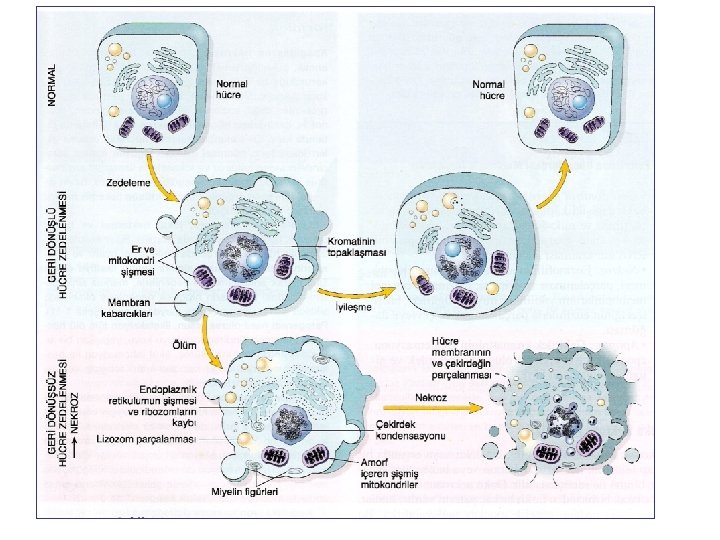

Normal hücre Hücre hasar etkeni Hücresel adaptasyon İrreversibl hücre hasarı Reversibl hücre hasarı Hücre ölümü Nekroz Apopitoz

• Hücre Zedelenmesi: 1. Geri Dönüşlü (Reversibl) 2. Geri Dönüşsüz (İrreversibl) Temel olay: Membran Hasarı • Önce fonksiyon kaybı, sonra morfolojik değişiklikler İskemi durumunda kalp kası hücreleri 1 -2 dk içinde kasılamaz hale gelir, 20 -30 dk sonra ölüm olur.

Zedelenmede morfolojik değişiklikler • Reversibl (geri dönüşlü) hasar - hücresel şişme - yağlanma (yağ metabolizmasında rol oynayan hücrelerde- karaciğer, kalp) mikroveziküler makroveziküler

Reversibl (geri dönüşlü) hasar • Hücre şişmesi (plazma membranındaki ATP bağımlı iyon pompası bozulur. ) • Mitokondri ve ER başta olmak üzere organeller şişer. • Ribozomlar granüllü ER’dan ayrılır- protein sentezi bozulur. • Plazma memb. da kabarcıklar ortaya çıkar. • Oksidatif fosforilasyonda azalma (mitokondride ATP sentezinin bozulması) → Anaerobik glikolizde artma • Laktik asit artışı • p. H düşmesi • Çekirdek kromatininde topaklaşma

İskemik ve hipoksik hücre hasarı: İrreversibl (geri dönüşsüz) hasar: (Geçiş noktası ? ) • Kritik olay: 1. Geri dönüşümsüz mitokondri hasar 2. Plazma ve organel membranlarında bozulma • Lizozom parçalanması – Sindirim enzimleri açığa çıkarorganeller parçalanır. • Nükleer büzüşme, parçalanma, erime • Myelin figürler: Hücre membranından oluşan büyük fosfolipid kitleleri